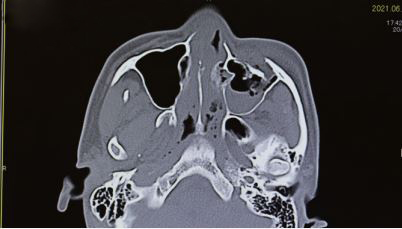

形成外科の治療対象は多岐にわたりますが、主な対象として、腫瘍、外傷、先天異常、美容外科が挙げられます。当院では美容外科、乳房再建以外のほぼすべての領域をカバーしています。腫瘍は皮膚・皮下の良性腫瘍、皮膚癌、外傷は顔面外傷、顔面骨骨折、熱傷、傷痕などの患者さんをご紹介いただいており、積極的に治療を行っています。特に顔面は整容的・機能的に重要な部分が集中しており、顔面を専門として扱う外科でもあります。生まれつきの病気は、目の変形(先天性眼瞼下垂、睫毛内反など)、耳の変形(副耳、耳前瘻孔など)、手足の変形(多指症、合指症など)などの小児形成外科分野の手術も積極的に行っており、機能的・整容的改善のみならず、患児の精神的な発育にも良い影響を与えます。眼瞼下垂は身近な疾患ですが、「瞼が下がってきた、ものが見えにくい、目が疲れる」などの症状が生活の質の低下を招きます。このような症状に対して手術により改善し、社会参加の機会を増やすことにも繋がります。また、治療対象は全身のあらゆる部位に及ぶため、形成外科単独で治療にあたるだけでなく、他の多くの診療科との連携においても、存在意義を発揮する分野であります。